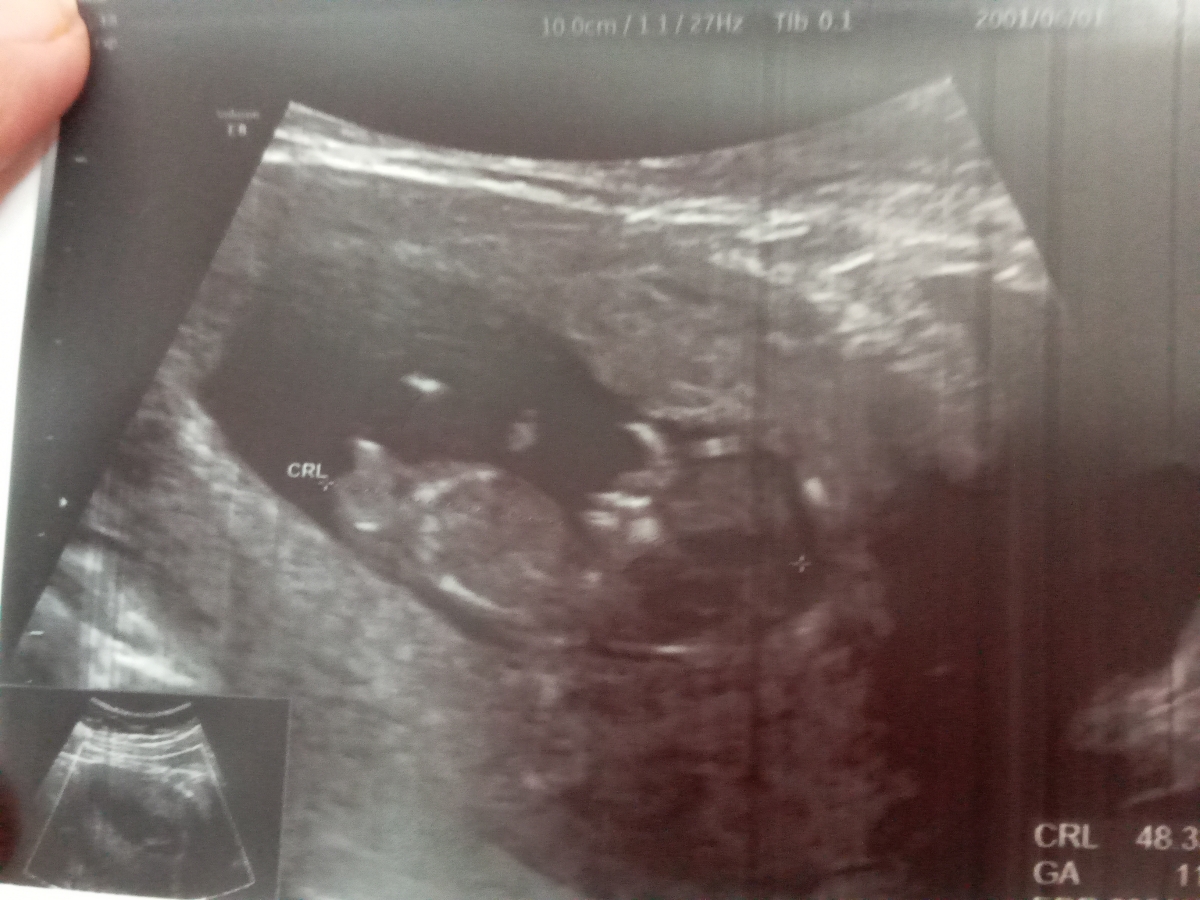

سونو NT انجام دادم میشه برا منم حدس بزنید نی نی چیه؟ دکترم احتمال داد بعدش میگم

😃منم تاریخ تقریبی زایمان رو زده ۱۴ اسفند